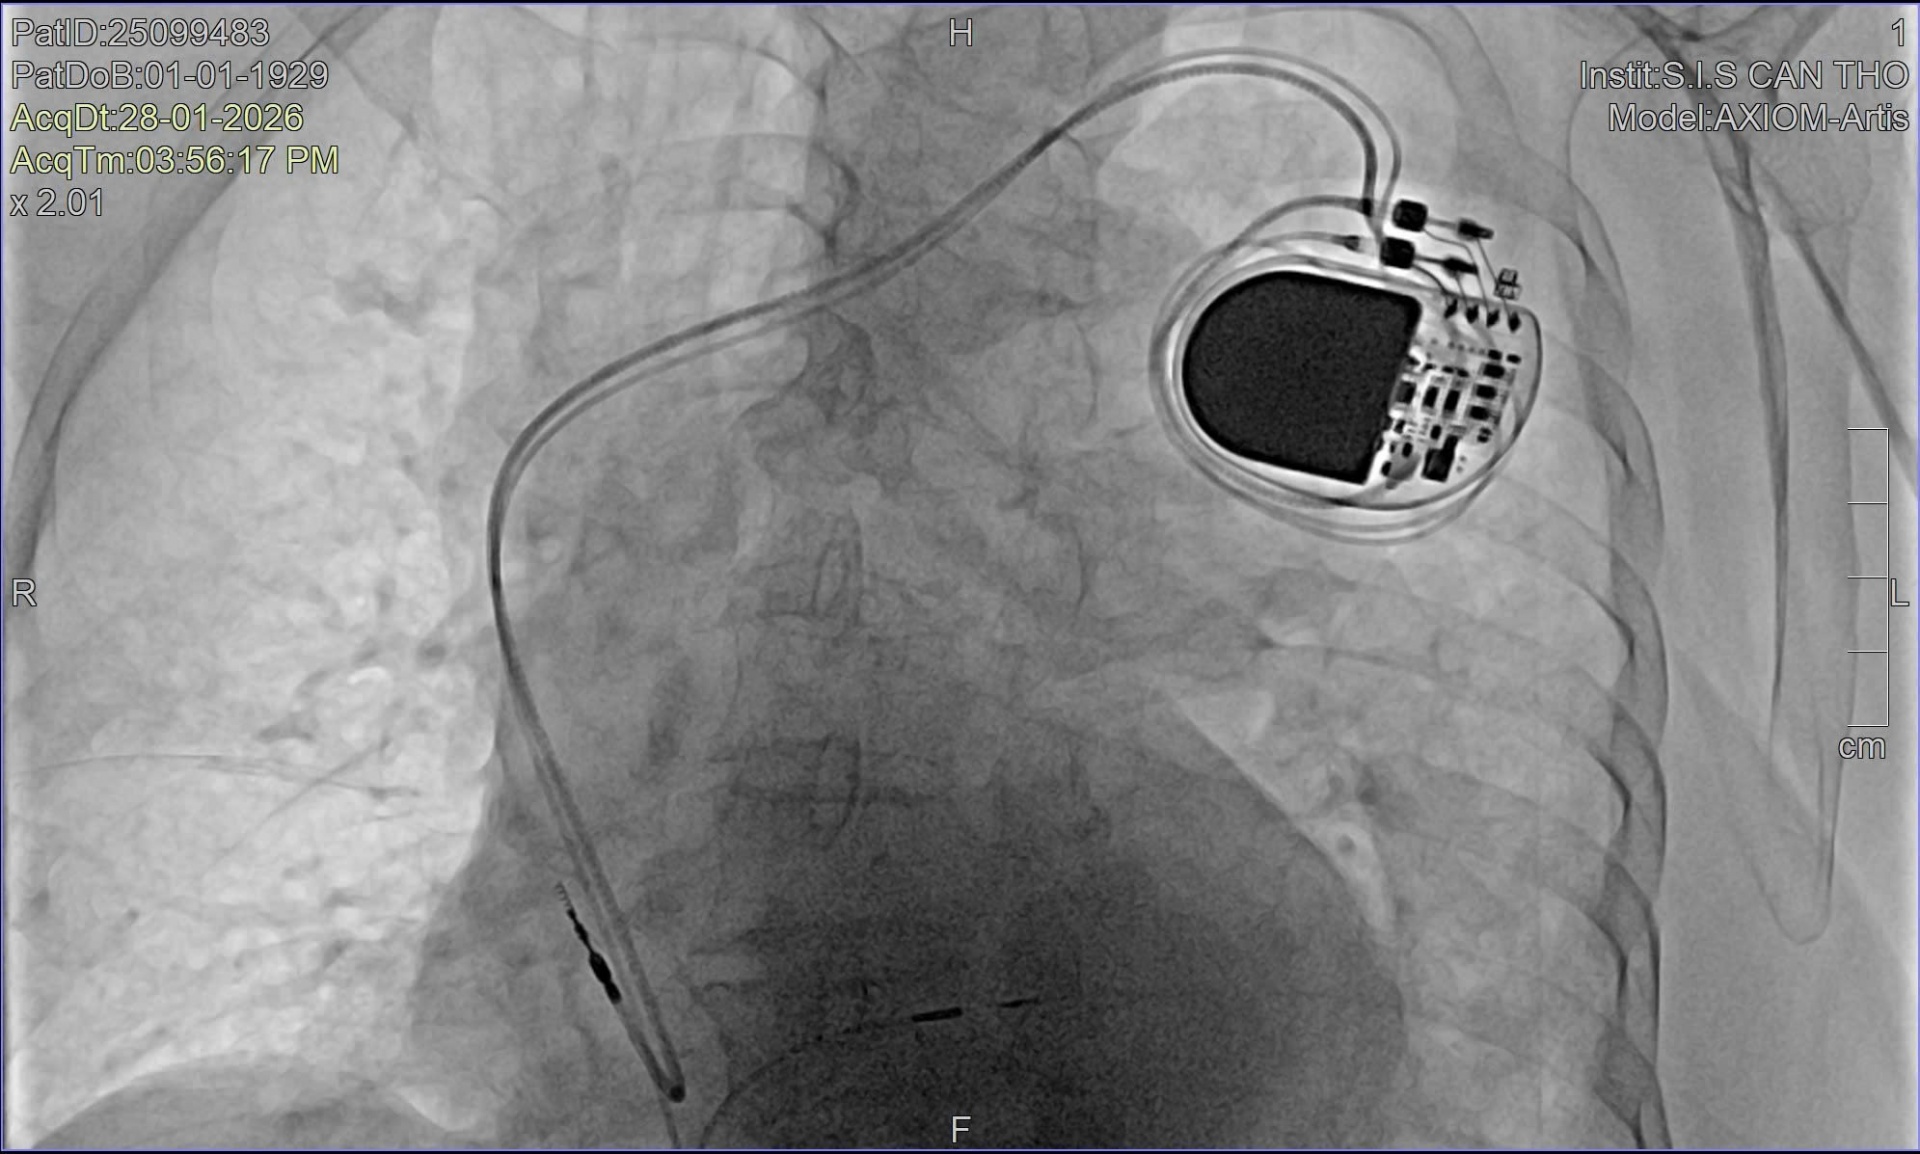

Theo BS.CKII Nguyễn Mạnh Cường, Phó Khoa Nội Tổng hợp, Bệnh viện Đa khoa Quốc tế S.I.S Cần Thơ, do bệnh nhân tuổi cao và tình trạng rối loạn nhịp nghiêm trọng, ê-kíp điều trị đã đặt máy tạo nhịp tạm thời nhằm hỗ trợ nhịp tim và ổn định huyết động ban đầu. Song song đó, bệnh nhân được thực hiện các xét nghiệm chuyên sâu như xét nghiệm máu, chụp X-quang phổi và chụp mạch vành bằng DSA.

Kết quả chụp mạch vành cho thấy bệnh nhân có hẹp mạch vành mức độ vừa, phù hợp với độ tuổi và được điều trị nội khoa. Sau khi tình trạng toàn thân ổn định, các bác sĩ tiến hành hội chẩn và thống nhất chỉ định cấy máy tạo nhịp vĩnh viễn bằng kỹ thuật bó nhánh trái - phương pháp tiên tiến đang được triển khai tại Bệnh viện.

“Đây là trường hợp bệnh nhân lớn tuổi nhất từng được điều trị bằng kỹ thuật này tại bệnh viện, với nhiều thách thức do tuổi cao và rối loạn nhịp tim phức tạp. Hiện nay, tại Việt Nam, vẫn còn rất ít cơ sở y tế có thể thực hiện kỹ thuật cấy máy tạo nhịp bó nhánh trái, chủ yếu tập trung ở những bệnh viện có đầy đủ trang thiết bị hiện đại và đội ngũ bác sĩ chuyên sâu về điều trị rối loạn nhịp tim. Khác với phương pháp cấy máy tạo nhịp truyền thống, kỹ thuật cấy máy tạo nhịp bó nhánh trái giúp nhịp tim được dẫn truyền gần với sinh lý tự nhiên, bảo tồn chức năng co bóp của thất trái và giảm nguy cơ suy tim về lâu dài. Đặc biệt, phương pháp này mang lại nhiều lợi ích cho người cao tuổi khi vừa đảm bảo hiệu quả điều trị, vừa hạn chế biến chứng”, BS. CKII Nguyễn Mạnh Cường cho biết.